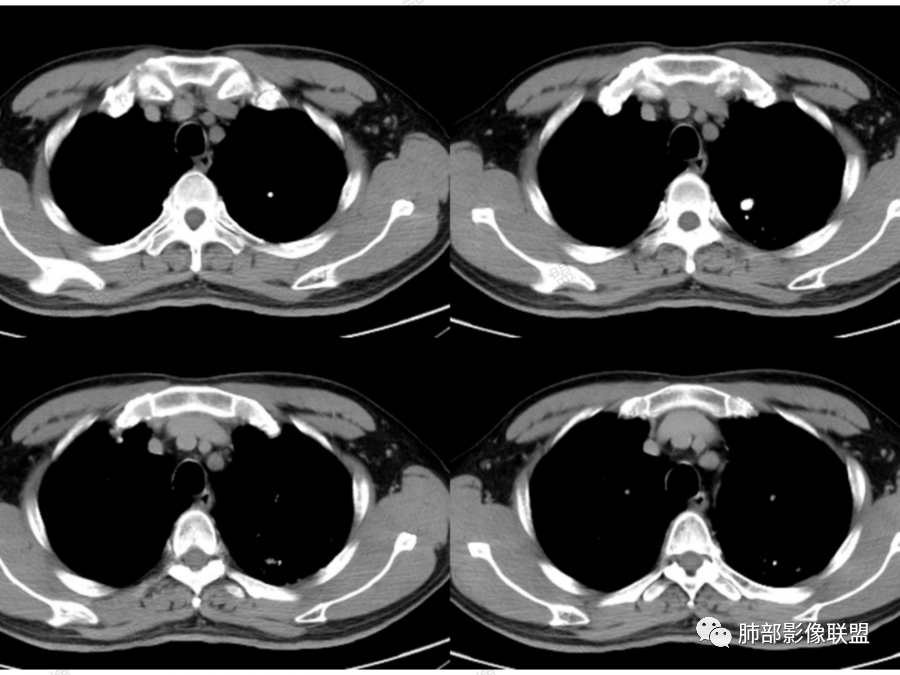

孤立性的多囊型病变伴分隔。ccam,肺隔离征,囊性肺癌,闭锁。。这是大家上面写的。看看怎么排除。血管看到肺动脉进入供血,没有感染液平,肺隔离不符合。没有代偿肺气肿,支气管没有闭锁,闭锁不考虑。那锁定ccam和肺癌。我们临床也常见是支气管畸形所致的囊。

@傅昌瑜—贺州市人民医院—呼内 里面的血管进一步支持恶性。但不鉴别腺癌和鳞癌,主要鉴别的,还是多囊,张力较高,囊壁较薄(实变区除外),加GGO。

5.病灶是否有分叶、毛刺、支气管截断、血管集束征、胸膜凹陷征等周围型肺癌的影像征象。应留意同侧肺门及纵隔有无增大淋巴结。